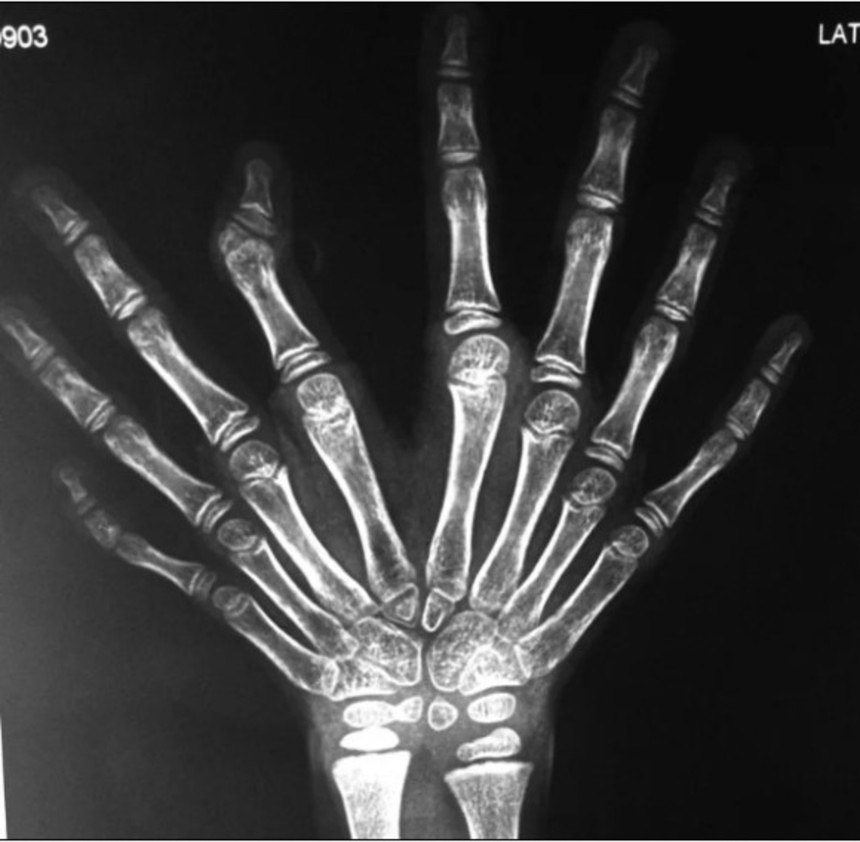

以下の画像は重複尺骨病の患者のレントゲン写真である。尺骨のほかに、手根骨、中手骨、指骨の重複が認められ、橈骨と親指の不在が見受けられる。写真の人差し指の第二関節には形成不全も見受けられる。

この画像を大きなサイズで見る似たようなケースはRadiopaedia.orgやNational Center for Biotechnology Informationにも記録されており、こちらは写真も記録されている。